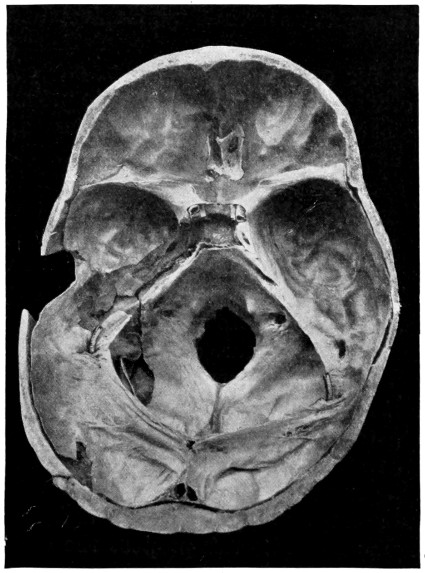

29 A and B. The base of the skull and the base as seen on transillumination 70, 71

50 A and B. The inner aspect of the skull and the same seen on transillumination 137